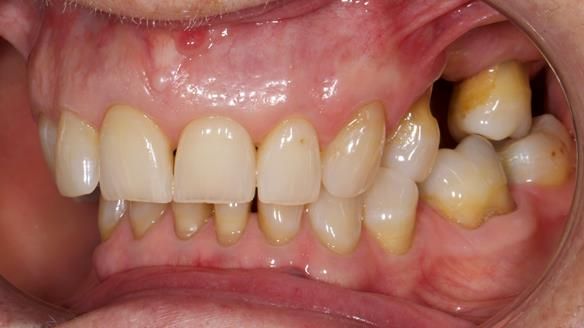

Joyce's Case Presentation 61

Welcome to Newsletter 61. In this edition, I walk through the process of creating and fitting a metal based lower partial denture for Joyce, a fit and healthy 76 -year-old woman.

Joyce self-referred to me for specialist prosthodontics.

The missing lower right teeth to be replaced with a metal based partial denture.

The detailed clinical situation and treatment process are outlined below, with clinical work provided by me and technical work by Rowan Garstang. The treatment spanned six visits for denture fitting and one review.